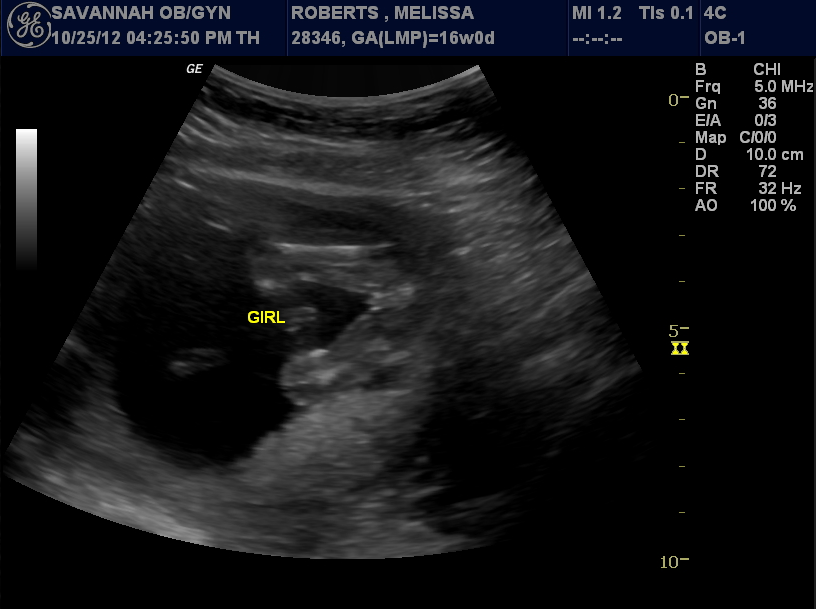

We are having a GIRL!!!!

We found out last Thursday, October 25th that we are expecting a little girl and we couldn't be more excited. We had out gender check ultrasound at 16 weeks where we got to see our little girl once again. At first she didn't want to cooperate. She was laying face down and very low. The ultrasound tech tapped my belly a few times and that must have waken her up because she was extremely active after that. She barely held still long enough to get a good look however, after about 10 minutes of looking and lots of fun pictures, we were able to get a good shot to determine that she is indeed a girl. She waved "Hi" and showed off her beautiful spine. She is much larger than the last ultrasounds that we had done. It is amazing how fast she is growing and how the time is flying by. She will be here before we know it.